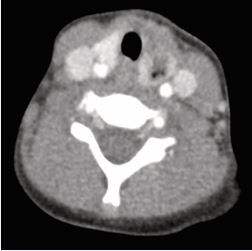

Flexible endoscopy confirmed the sinus tract, aided by visualization of a characteristic mucosal fold (Figure 2).

Figure 2 Flexible endoscopy showing an internal opening in the left pyriform sinus. A mucosal fold medial to the opening (arrow) helped localize the tract.

Most reported cases are left-sided [9-17], likely due to embryological and vascular asymmetry, including the longer course of the left tract and its descent below the aortic arch [3]. Clinically, a fourth branchial cleft sinus should be suspected in children with recurrent neck infections or episodes resembling suppurative thyroiditis. Misdiagnosis may lead to unnecessary procedures such as thyroidectomy, which does not address the underlying cause [17]. Our series demonstrates that flexible laryngoscopy, combined with gentle oxygen insufflation, can reliably identify the internal tract opening, obviating the need for rigid laryngoscopy. Flexible laryngoscopy offers several advantages, including wide availability, reduced need for general anesthesia, and avoidance of radiation exposure. This is especially valuable in pediatric patients, in whom anatomical constraints make rigid laryngoscopy more challenging and less sensitive [17]. We suggest that insufflation assists in dilating the sinus opening, improving visualization of characteristic features such as the mucosal fold or “flange” medial to the sinus opening and lateral to the upper esophageal sphincter, an anatomical landmark rarely mentioned in the literature [10-11] (Figure 2). Notably, we report for the first time a double-lumen pyriform sinus opening (Figure 7), potentially representing an anatomical variant. Flexible endoscopy may also reduce the need for imaging, particularly CT scans, which involve radiation. Ultrasound, a radiation-free modality, can aid in identifying abscesses or thyroid involvement and serve as an adjunct in evaluation, and waive the need for additional unwarranted imaging as CT.